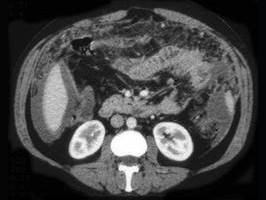

问题 女,36岁,低热、乏力,腹胀不适一月余,结合影像检查,应考虑为 ( )

选项 A.肝硬化腹水 B.结核性腹膜炎 C.腹腔转移瘤 D.心源性腹腔积液 E.急性化脓性腹膜炎

答案 B